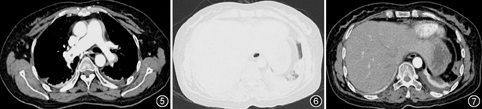

患者女,50岁,因"下肢肿胀疼痛半个月,晕厥、气促4 d,胸痛1 d"于2015年8月30日入院。患者2015年8月11日于外院行"清宫术"后阴道流血,给予"酚磺乙胺"静脉滴注7 d,用药期间右下肢逐渐出现肿胀、疼痛,诊断为"风湿病"并给予消炎镇痛治疗后疼痛减轻,但肿胀无改善。3 d前患者突发晕厥,约10 s后意识恢复,自觉气促、胸闷。下肢彩色多普勒超声检查示:右侧股总、股浅、腘静脉、胫后近段静脉血栓(完全性),诊断"下肢静脉栓塞" 。转至上级医院给予抗凝治疗伊诺肝素钠0.4 ml皮下注射,12 h/次。患者凌晨自觉右侧胸痛,行CT肺动脉造影(CTPA)检查示:双肺动脉主干栓塞,骑跨型肺栓塞,未见明显肺梗死(图1图2图3),为进一步诊治转入我院。既往史:甲状腺功能亢进病史3年,规律服用"甲硫咪唑"治疗,半年前曾经出现右小腿疼痛、稍肿胀自行好转无就医。否认脑血管意外、高血压病史,平素血压约120/70 mmHg(1 mmHg=0.133 kPa),近期无腰椎、眼部手术史,否认服用避孕药、雌孕激素及糖皮质激素史。家族史:母亲及2位妹妹均有下肢深静脉栓塞病史。个人史:无特殊。入院体检:体温36.5 ℃,脉搏80次/min,呼吸24次/min,血压119/71 mmHg,SpO2 93%(吸氧3 L/min),体重61 kg。口唇无发绀,双肺呼吸音清,未闻及干湿性啰音。腹平软,无压痛、反跳痛,肝脾不大,肝肾区无叩击痛。右下肢肿胀,皮温稍高,肌力正常,无感觉功能减退。入院相关检查:血气分析:pH值为7.41,吸氧浓度(FiO2) 30%,PaO2为94.3 mmHg,PaCO2为38.3 mmHg,肺泡动脉氧分压差[P(A-a)O2] 67.9 mmHg;凝血功能:D-二聚体(ELISA法)>10 000 ng/ml,凝血酶原时间 (PT) 14.7 s ,活化部分凝血活酶时间 (APTT) 44.2 s,凝血酶时间(TT) 15.4 s,纤维蛋白原3.30 g/L;心肌损伤相关检查:谷草转氨酶:41.6 U/L,肌酸激酶:15.4 U/L,肌酸激酶MB同工酶:12.0 U/L,乳酸脱氢酶:294.4 U/L,肌钙蛋白(CTnI)0.1 μg/L,肌红蛋白:7.5 μg/L;易栓症相关检查:蛋白S 11%,蛋白C 53%,抗凝血酶Ⅲ 65%。下肢深静脉彩色多普勒超声示:右股总静脉远端至小腿段完全性栓塞,伴丰富的侧支循环,右股总静脉近心端及大隐静脉未见异常团块。心电图未见明显异常(图4)。心脏彩色多普勒超声提示右心增大,三尖瓣反流(轻度),肺动脉高压(轻度),左心室收缩功能未见异常。入院后根据体重给予伊诺肝素钠0.6 ml,1次/12 h皮下注射,第2天患者气促较前加重。体检:呼吸急促,三凹征,呼吸27次/min,脉搏氧饱和度(SpO2)90%(吸氧4 L/min),血压103/62 mmHg。考虑病情较前加重,为避免病情恶化与家属充分沟通并签署同意书后,给予重组人组织纤维蛋白溶酶原激活剂(rt-PA)50 mg,2 h方案溶栓治疗[1]。溶栓过程顺利患者无出血、无不良反应。溶栓后患者气促、胸痛症状明显好转,体检:呼吸22次/min,SpO2 96%(吸氧2 L/min),血压113/71 mmHg。间隔2 h复查APTT减至60 s后给予续贯低分子量肝素(药物、剂量同前)抗凝治疗。溶栓后第2天无明显诱因出现左季肋区疼痛明显,深呼吸加重,腹部无压痛、反跳痛,复查血常规血红蛋白未见明显降低,急查血淀粉酶30 U/L,脂肪酶225 U/L,腹平片排除胃穿孔及肠梗阻。给予对症止痛治疗效果不明显。溶栓后第4天复查胸部CT造影对比溶栓前CT示:(1)双侧肺动脉主干血栓消失、右下肺基底段肺动脉栓塞较前明显改善;(2)左下肺外基底段肺梗死(图5图6图7);腹部增强CT提示:腹部未见异常。考虑溶栓后肺动脉内血栓分解脱落栓塞远端肺动脉,导致肺梗死。继续予以足量低分子量肝素抗凝、吸氧、止痛等对症支持治疗,症状逐渐减轻好转,继续治疗1周后下肢血栓较前减少,9月13日出院,出院给予口服利伐沙班15 mg,2次/d,连续服用3周后改为20 mg,1次/d。

肺栓塞治疗方案需要根据病情及时调整,尤其是骑跨型肺栓塞。本例患者入院时血流动力学尚稳定,根据2014 ESC肺栓塞指南风险评估属于中高危组[8],密切观察下给予低分子量肝素抗凝治疗,治疗后症状加重、血压下降需要及时解除肺动脉梗死、恢复血流动力学立即给予溶栓治疗,治疗后患者症状明显改善。骑跨型肺栓塞血栓负荷重、血栓受血流不断冲击容易碎裂,尤其溶栓后血栓易碎裂为小块血栓随血流堵塞远端血管出现肺梗死。本例患者溶栓后第2天出现胸痛,相关检查排除了急腹症、腹腔内出血,复查血浆D-二聚体浓度逐渐下降可排除血栓复发。对比溶栓前及胸痛后复查胸部CTPA发现原主干内血栓消失,左下肺动脉内发现血栓该血管供应区域肺组织出现梗死灶。由此考虑溶栓后继发肺梗死继续给予足量抗凝及对症治疗,治疗后症状逐渐改善好转。结合本例患者治疗过程及查阅文献,我们认为骑跨型肺栓塞治疗原则与其他类型肺栓塞相同,对血流动力学异常者需要及时溶栓治疗,对血流动力学稳定者可以给予足量抗凝治疗,但是由于血栓负荷重、病情变化快需要密切观察及时调整治疗方案。本例治疗经验显示,骑跨型肺栓塞溶栓或抗凝治疗后可能出现远端肺梗死导致胸痛,溶栓继发肺梗死给予足量抗凝治疗有效死亡率及出血风险并未增加但需要排除脏器出血及急腹症。通过对该病例报道和分析以期提高对骑跨型肺动脉栓塞诊断和治疗认识。